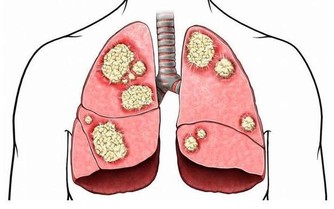

這種從肛門排出的廢氣,有時會帶有臭味;這是因為排氣時人體會釋放少量氫化硫,而這種物質具有防止細胞受損的作用,甚至可以預防心血管疾病和中風。

在放屁時不應出現不適感,氣味雖然難聞但不會極端惡臭。如果發現自己在排氣時,明顯感到腹痛,或是氣味比較異常,那麼應當立即去醫院進行相應檢查,食物不耐受和結腸癌等疾病都會引起這類病症。